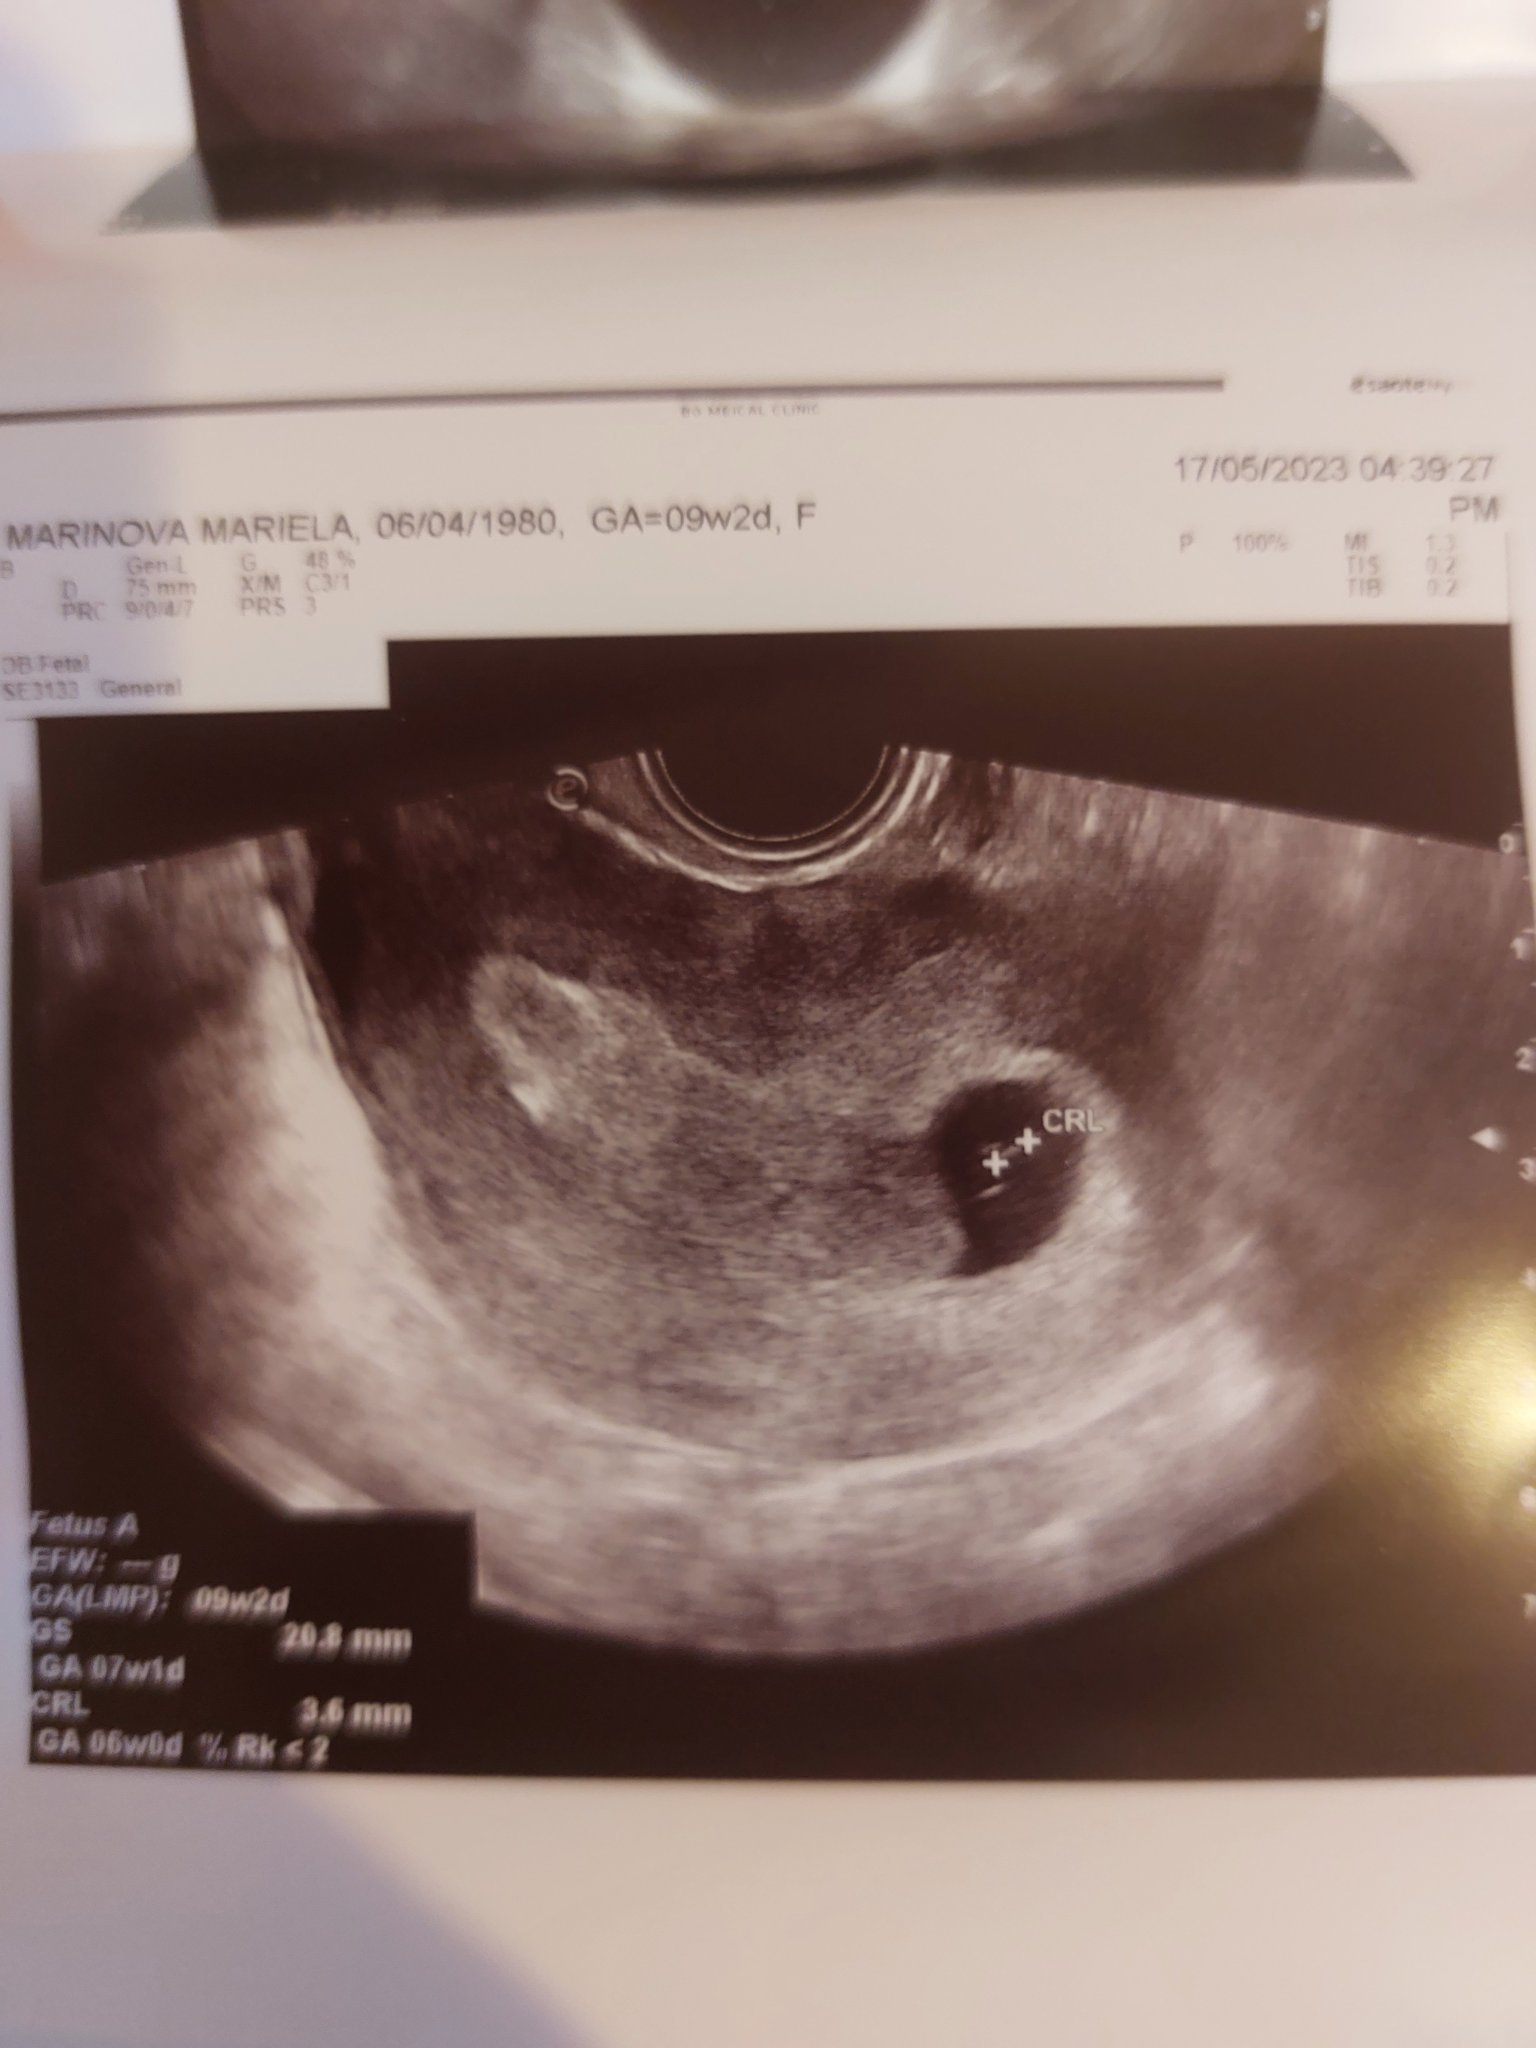

Здравейте , аз съм нова тук.  Бих искала да ми кажете мнението си за последните ми снимки - 9г.с и два дни - лекарят каза , че ембриона е спрял да се развива след 6та седмица. Каза да спра прогестерона и да чакам до 2-3 дни да получа спонтанен аборт.  Вие какво мислите .

Също така последната снимка, която ще кача е от предходния скан и не разбирам защо CRL е по голям -4.8мм , а снимката е от по ранна дата 05.05.2023 ???

Съжалявам за този развой. Но наистина размерите са на 6 седмично бебе и няма как, при положение, че трябва да си в девета г.с. да изостава толкова много. Пише по-голяма стойност, защото в тези ранни седмици е доста трудно да хване доктора точно началото и края на ембриончето, а това е 1 мм разлика. Би могла да отидеш на второ мнение, но ехографската снимка изглежда добра и надали докторът е сбъркал

Здравей, благодаря ти за истинското и откровено мнение . Аз имам малки съмнения все още , понеже знам точно кога е поставен ембриона ( понеже е инвитро ) -27.март.2023.  Но докторите изчисляват бременността с две седмици повече защото , започват да броят от първия ден на последния менструален цикъл - при мен беше 13.март. 2023.  Затова съм объркана. Ако смятам бременността от датата на имплантиране на ембриона са 7г.с и 2дни , но ехографа ги изчислява 9г.с и два дни.